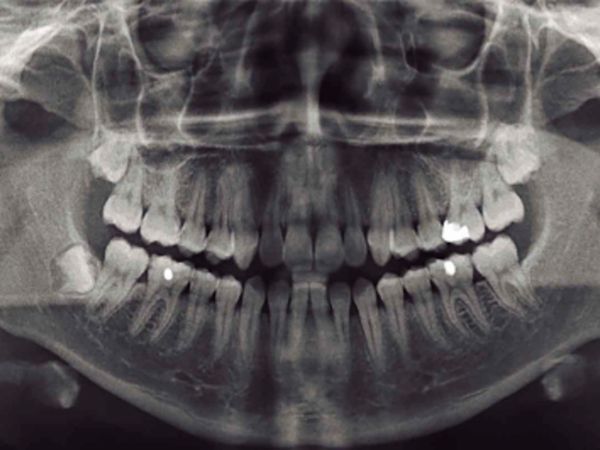

Terceros Molares

Los terceros molares o muelas del juicio son las ultimas en salir, por lo tanto no hay suficiente espacio para que erupcionen adecuadamente, causando dolor e inflamación, siendo indicación para ser extraídas. Este procedimiento se puede realizar bajo anestesia local solamente y ademas bajo sedación endovenosa. Contamos con el equipo necesario para realizarlo.